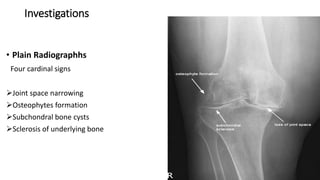

Investigations

• Plain Radiographhs

Four cardinal signs

Joint space narrowing

Osteophytes formation

Subchondral bone cysts

Sclerosis of underlying bone